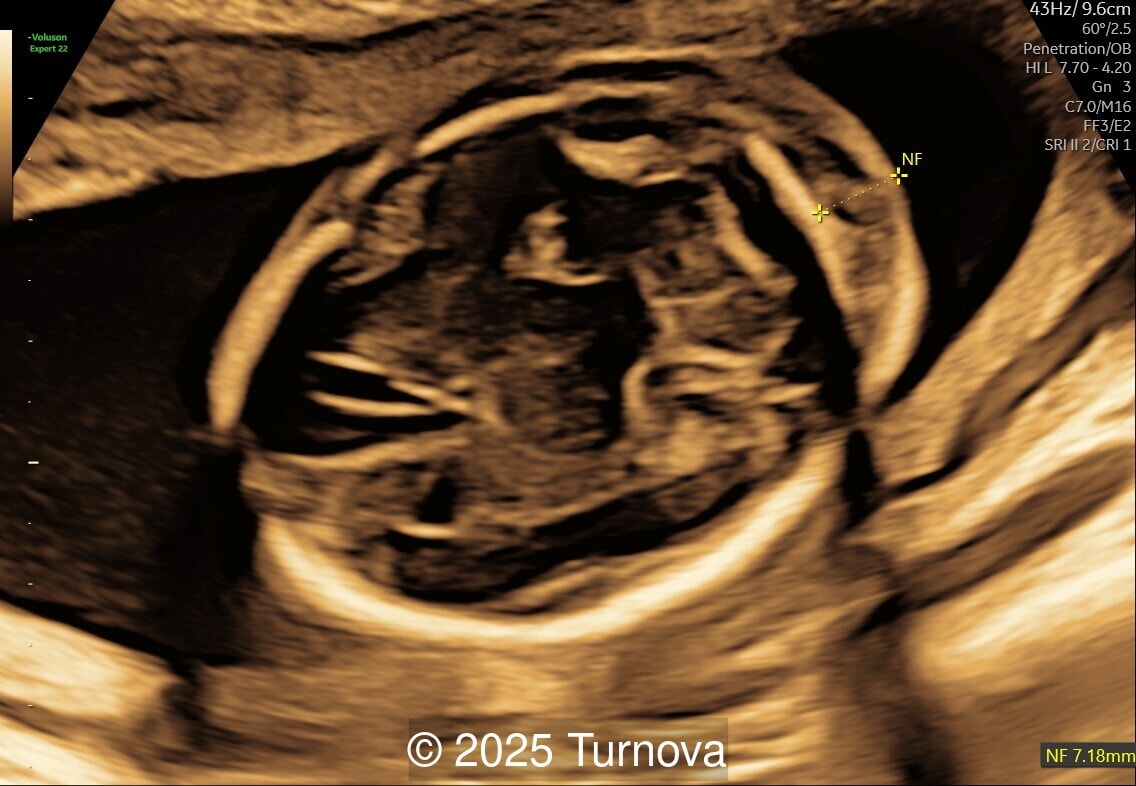

Image 1

A 32-year-old gravida 2, para 1 presented at 19 + 0 weeks of gestation for a routine second-trimester screening ultrasound. Ultrasound examination revealed abnormal subcutaneous tissue and abnormal nuchal fold highly suggestive of trisomy 21. In addition, a marked hepatomegaly was noted, with the liver appearing diffusely hyperechogenic. No ascites or signs of hydrops were present.